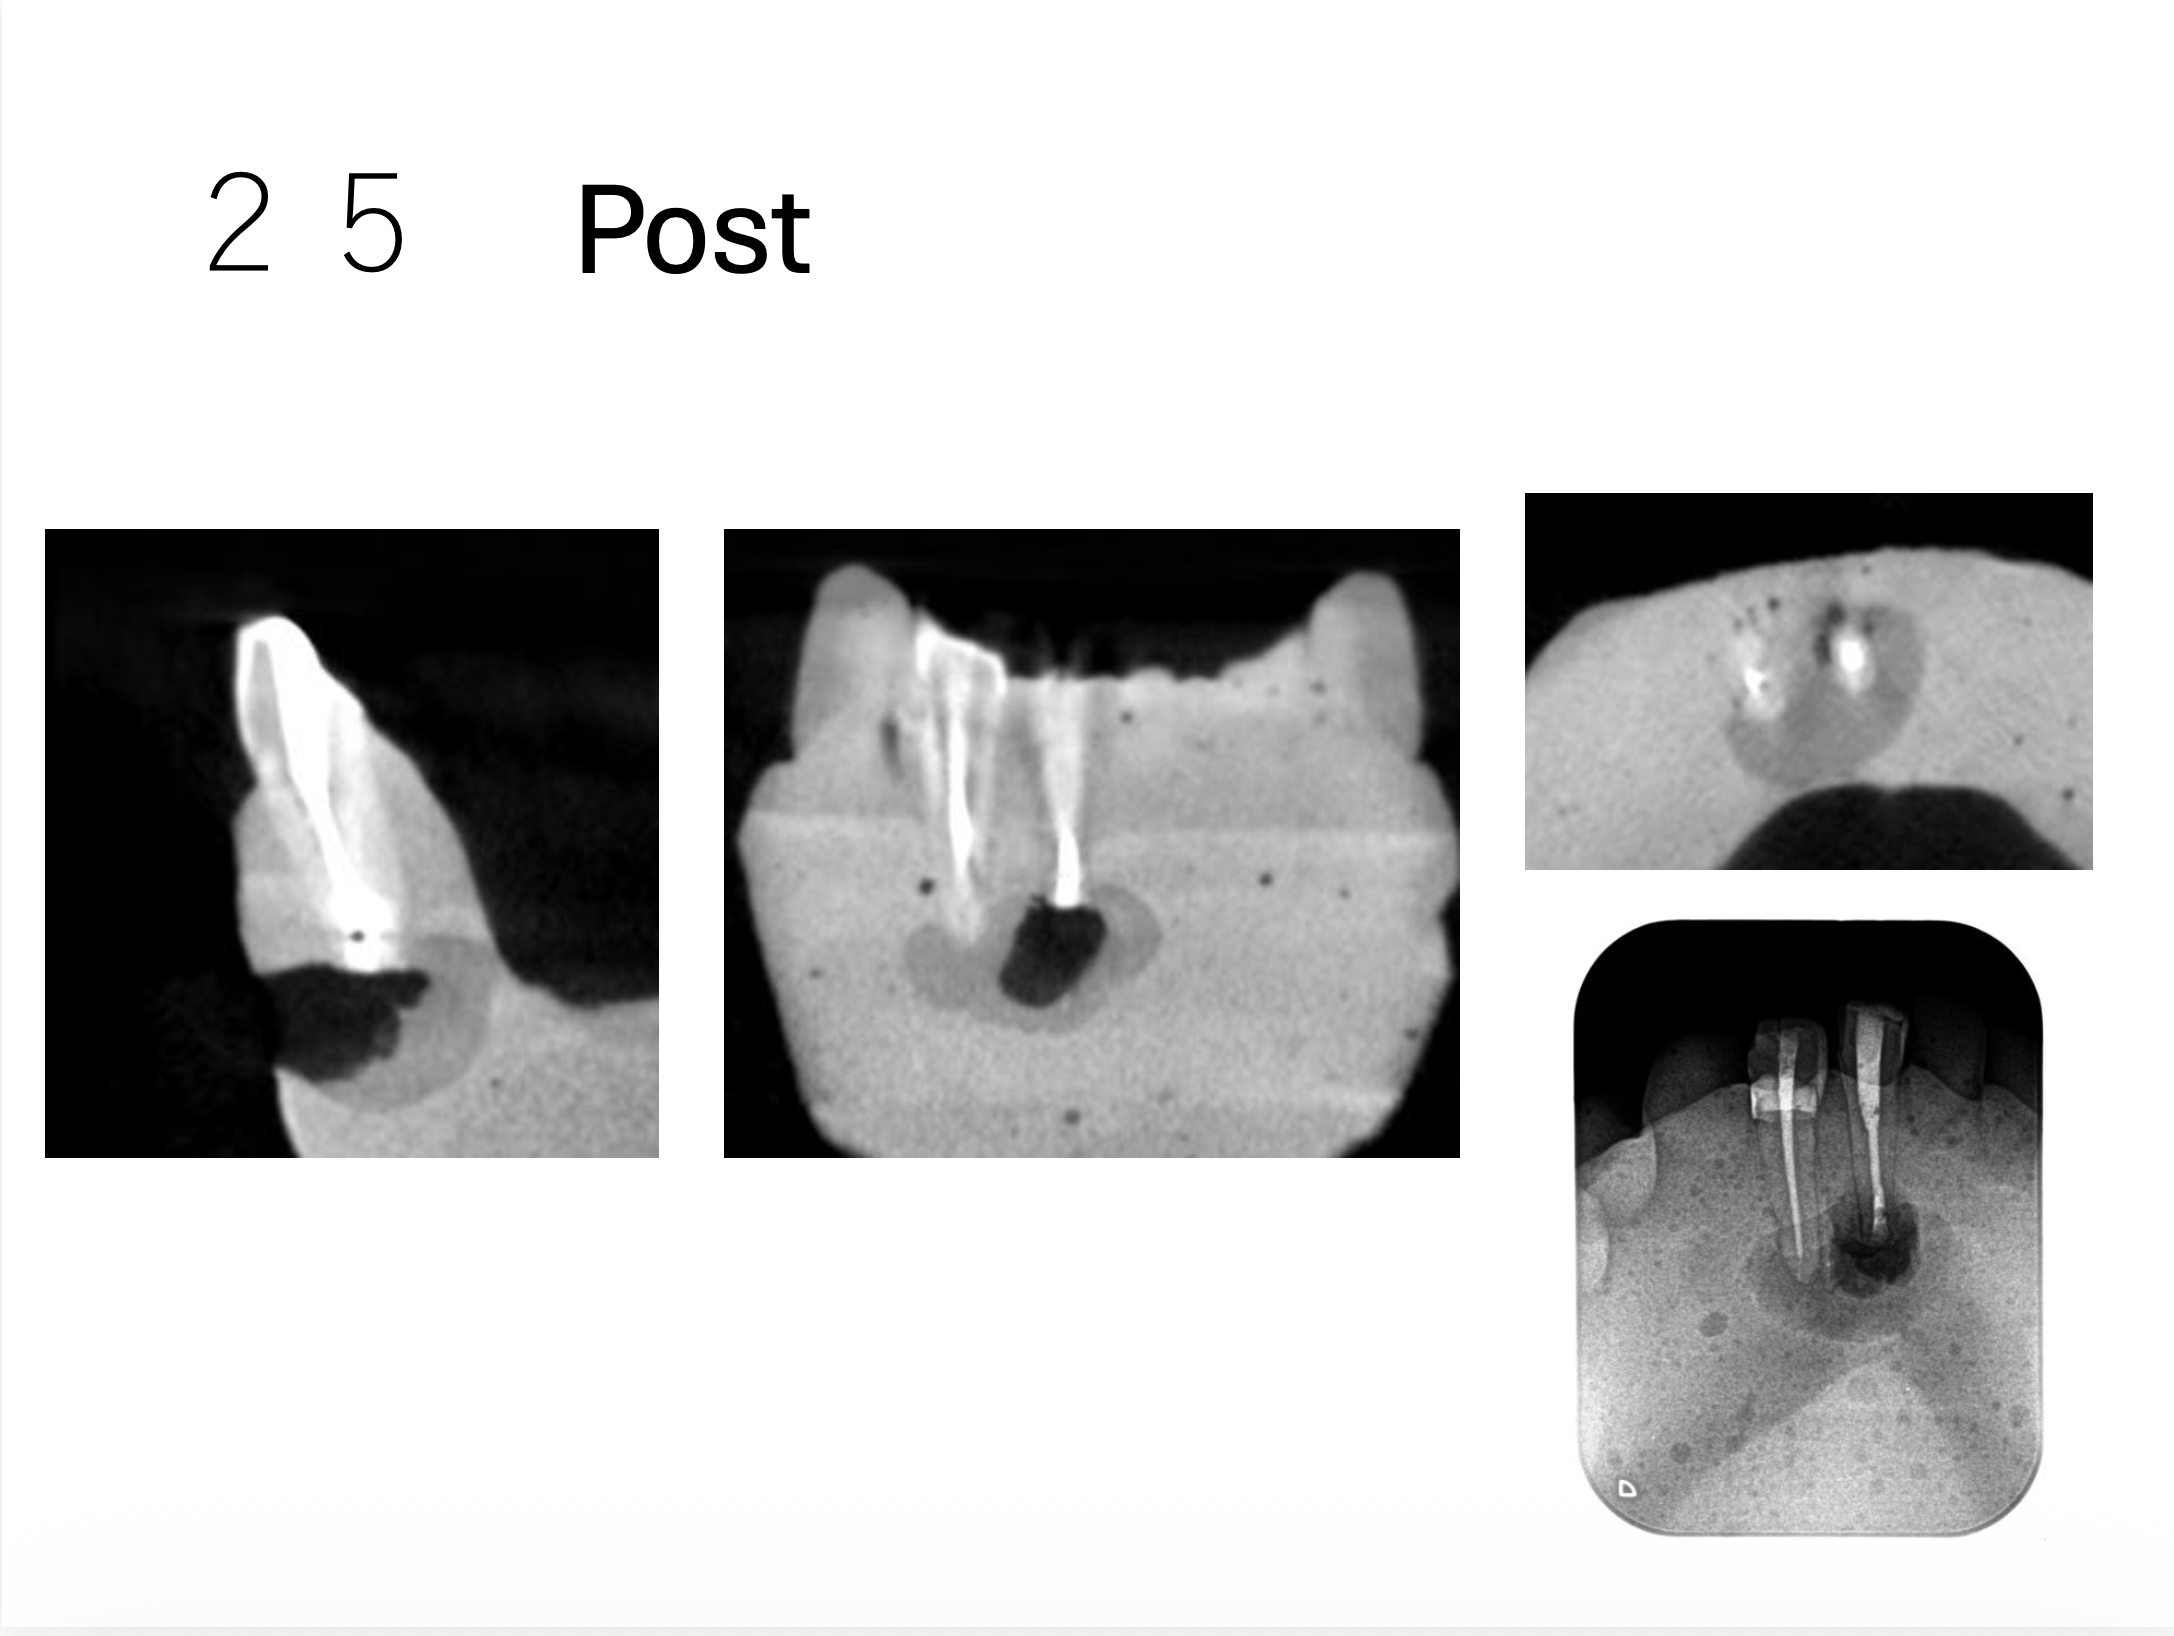

Intentional Replantationも問題なくできている。

次の受講者は以下だ。

これでも治癒することはこのHPのBlogで示しているが、

USCだとしょっぱいからやり直せと言われる案件だ。